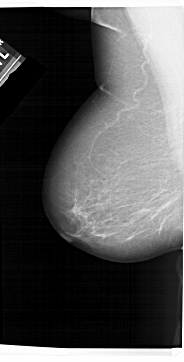

A_1309_1.RIGHT_MLO

LEFT_MLO LINES 6871 PIXELS_PER_LINE 3496 BITS_PER_PIXEL 12 RESOLUTION 43.5 NON_OVERLAY